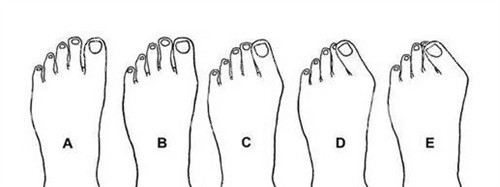

苏敬达的诊疗范围十分广泛,除了核心的拇外翻矫正与失败修复,还涵盖宽足缩窄、长趾缩短、足趾畸形矫正、足型美化等多个足部项目。

比如有些人不仅有拇外翻,还伴随足型过宽影响穿鞋美观,苏敬达能在矫正拇外翻的同时,结合宽足缩窄项目进行改善;对于足趾长短不一、形态畸形的情况,也能通过正规诊疗进行调整,让足部形态更协调。